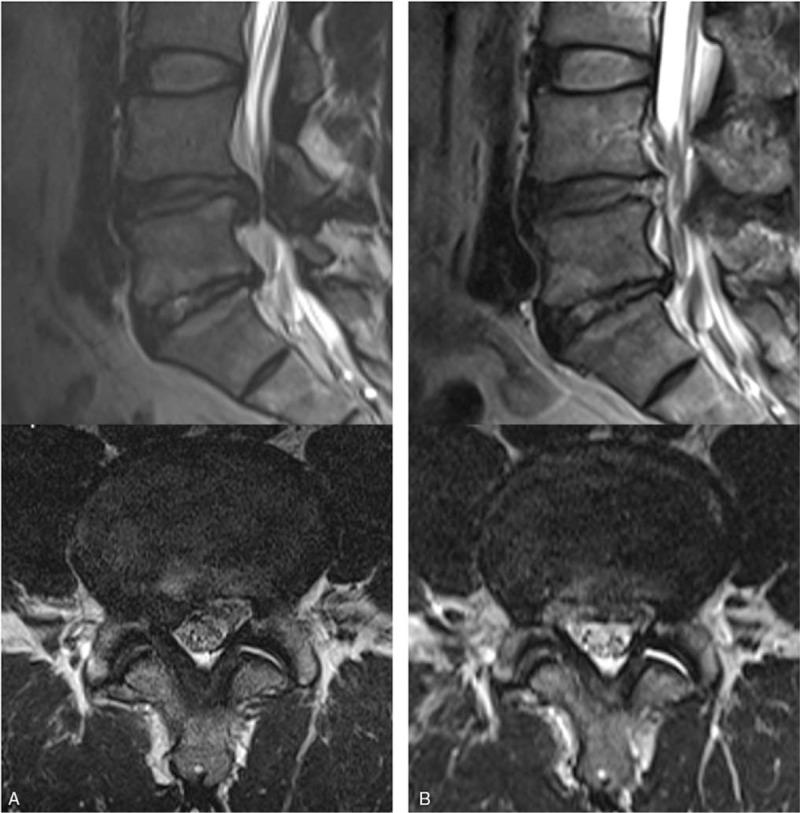

Although several studies have reported the effectiveness of transforaminal full-endoscopic lumbar discectomy (TELD), no cohort study on the long-term outcomes of TELD has been conducted. Thus, this study aimed to evaluate the long-term clinical outcomes of TELD and to determine the factors predicting favorable outcome.Five-year longitudinal data of 204 consecutive patients who underwent TELD were collected. Outcomes were assessed using the visual analog scale (VAS) pain score, Oswestry disability index (ODI), patient satisfaction rating, and the modified Macnab criteria.The mean VAS score for leg pain improved from 7.64 at the baseline to 1.71, 0.81, 0.90, and 0.99 at postoperative 6 weeks, 1 year, 2 years, and 5 years, respectively (P <.001). The mean ODI improved from 67.2% at the baseline to 15.7%, 8.5%, 9.4%, and 10.1% at postoperative 6 weeks, 1 year, 2 years, and 5 years, respectively (P <.001). The overall patient satisfaction rate was 94.1%. Based on the modified Macnab criteria, 83.8% of patients had excellent or good results. In this study, younger patients with intracanal disc herniation tended to have better outcomes than elderly patients with foraminal/far-lateral disc herniation (P <.05).Transforaminal endoscopic lumbar discectomy offers favorable long-term outcomes with minimal tissue damage. Postoperative pain and functional status may change over time. Proper patient selection remains essential for the success of this minimally invasive procedure.

尽管多项研究报告了经椎间孔全内镜下腰椎间盘切除术(TELD)的有效性,但尚未进行关于TELD长期疗效的队列研究。因此,本研究旨在评估TELD的长期临床疗效,并确定预测良好疗效的因素。收集了204例连续接受TELD治疗患者的5年纵向数据。使用视觉模拟量表(VAS)疼痛评分、Oswestry功能障碍指数(ODI)、患者满意度评分和改良Macnab标准评估疗效。腿痛的平均VAS评分从基线时的7.64分别改善至术后6周、1年、2年和5年的1.71、0.81、0.90和0.99(P<0.001)。平均ODI从基线时的67.2%分别改善至术后6周、1年、2年和5年的15.7%、8.5%、9.4%和l0.1%(P<0.001)。总体患者满意度为94.1%。根据改良Macnab标准,83.8%的患者结果为优或良。在本研究中,椎管内椎间盘突出的年轻患者往往比椎间孔/极外侧椎间盘突出的老年患者疗效更好(P<0.05)。经椎间孔内镜下腰椎间盘切除术具有良好的长期疗效,且组织损伤最小。术后疼痛和功能状态可能随时间变化。正确选择患者对于这种微创手术的成功仍然至关重要。